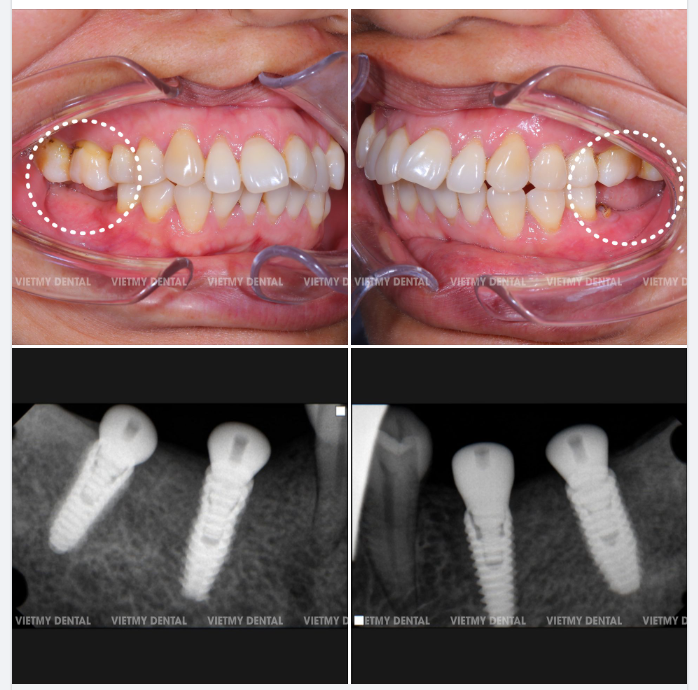

Trồng Răng Implant

Trồng Răng Implant -